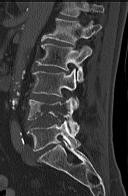

Figures 1 through 3 show the radiograph and CT images of a 68-year-old

woman who sustained a cervical injury after tripping over her cat. She has mild facial trauma, which includes a broken upper incisor and a nonsurgical nasal fracture. She is neurologically intact. Her past medical history is consistent with obstructive sleep apnea, non–insulin-dependent diabetes mellitus (hemoglobin A1c level of 9.0), and morbid obesity, with a body mass index of 40. What is the preferred treatment for this patient?

4. Anterior odontoid screw fixation Discussion: C

Posterior C1-2 fusion with instrumentation provides stability and pain relief with excellent clinical outcomes despite the loss of C1-2 motion. Hard collar immobilization and halo vest immobilization both carry a substantial risk of nonunion in this patient because of her age, fracture displacement, residual fracture gap, and medical condition. Anterior odontoid screw fixation theoretically preserves C1-2 motion. In this case, the fracture is not reduced. Concentric reduction is a requisite for osteosynthesis of the odontoid. Her body habitus also may not allow anterior odontoid fixation.